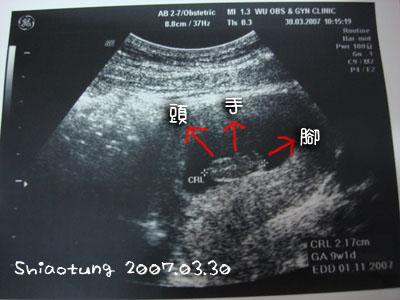

去那邊以後馬上就照超音波,

照了超音波看到寶寶,

沒想到才一個星期就長了一公分多....

上星期五0.59cm,

這次已經有2.17cm,

主要是看到頭形、手和腳!

我本來實在看不出來,

醫生說:手一直揮啊!有沒有看到?那就是手。

哇塞...真的很妙內!

有看到一根細細的東西一直揮,

不知道是揮還是在漂,

動很快,

姑且算他在跟我招手吧!!